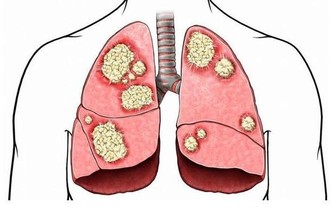

Honey仔之所以介紹這項研究的結果,除了想說明這種疾病的危險來源之外,還想提示人們,除了遺傳因素無法改變之外,食物因素是可以改變的。而體能也有很大關係,因為體能在很大程度上意味著代謝能力。人體的血尿酸當中,三分之二以上為內源性尿酸,食物來源只是小部分。這些尿酸70% 靠腎臟排泄,只有在人體代謝紊亂,產生較多內源性尿酸,而腎臟功能又不足以及時處理多餘尿酸的時候,才會出現高尿酸血症的情況。所以,提高身體對尿酸的代謝能力,要比斤斤計較食物的嘌呤含量更為重要。